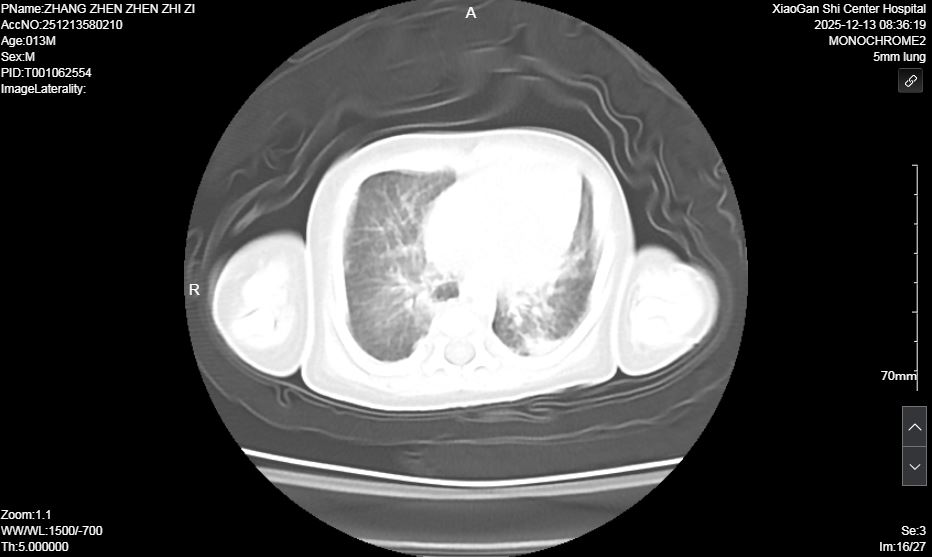

患兒入院后,NICU團隊立即啟動危重新生兒搶救預案。經快速檢查,初步診斷為宮內感染所致的足月兒急性呼吸窘迫綜合征(ARDS),該疾病極易合并肺高壓、氣胸、肺出血、呼吸衰竭等嚴重并發(fā)癥,屬于新生兒急危重癥,救治難度極大。團隊立即按新生兒ARDS診療規(guī)范進行氣管內給予肺表面活性物質,循環(huán)支持,抗感染、持續(xù)機械通氣、營養(yǎng)支持等對癥治療。然而,由于原發(fā)疾病嚴重,患兒經歷7天機械通氣后,病情出現(xiàn)反復,肺部影像學顯示雙肺實變明顯,脫氧撤機困難。

術前肺部超聲及CT均提示雙肺實變明顯

面對挑戰(zhàn),新生兒科迅速啟動多學科會診(MDT),聯(lián)合呼吸內科、兒童呼吸科、中心試驗室等科室專家深入討論。在充分與家長溝通并取得同意后,醫(yī)療團隊成功為患兒實施了本市首例新生兒纖維支氣管鏡和肺泡灌洗術,同時取灌洗液進行 NGS檢查、明確病原學診斷,團隊快速調整個性化診療方案,精準調控參數(shù)、嚴密監(jiān)測病情,穩(wěn)步推進階梯式撤機脫氧,全力攻克救治難關。